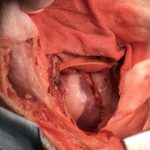

5歳の柴犬が最近、呼吸が早いとのことで主治医を受診しました。主治医のもとで胸水の抜去を行なったところ、乳び胸水の貯留が確認されました。精査と外科的な治療目的で紹介受診されました。CT検査および各種検査で乳び胸の原因となる腫瘍性疾患、寄生虫疾患、心臓疾患、外傷などは除外されました。十分な鎮痛処置を行なったのち右側開胸・開腹アプローチにより、結腸リンパ節からインドシアニングリーンにより胸管造影検査を行いました。造影により大動脈の背側に2本の胸管の走行が目視で確認されました。大動脈からこれを慎重に分離、チタンクリップで5箇所の結紮を行いました。さらに、横隔膜にウインドウを形成し、腹腔内から大網を牽引し、胸腔内で固定しました。さらに、慢性の乳び貯留による臓側の胸膜炎に伴い、著しく肥厚した心膜を横隔神経より腹側領域のを超音波メスにより切除を実施しました。この患者さんには胸管結紮、大網置換術、心膜切除術、これらの術式を組み合わせて手術を実施しました。トータルの手術時間はおよそ150分でした。術後5日に乳びの貯留が消失したため退院となりました。柴犬においてこの病気を経験する事が多いため、獣医師の仲間に尋ねると、どうも遺伝的な背景が関与しているようです。今回の手術で完治しなければ、デンバーシャントなどのインプラントの埋入を行う予定です。